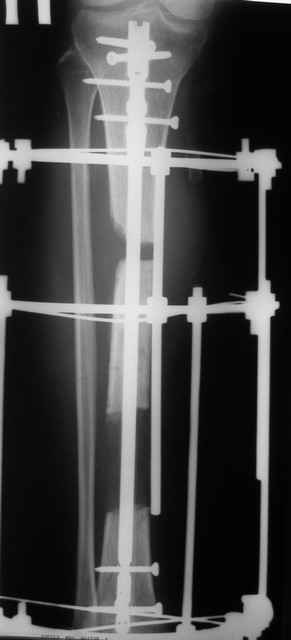

Лично мне никогда не нравилась тактика низведения фрагментов, а после плотного знакомства с работами Александра Лернера я стал однозначным сторонником тактики острого укорочения, используя её не только в свежих случаях, но и в застарелых, и даже совсем застарелых...

Добавляю свой пятак, не дожидаясь завершения случая, который приберегал "на третье". Выбрал фото мягких тканей.

Кратко: мужчина за 60 лет получил травму 28 лет назад (переехало автобусом). Оперировался десятки раз, в итоге с очередным патологическим переломом, хронической язвой и гипсовой лонгетой попал ко мне... Объективно - остеомиелит, инфицированный ложный сустав (или как его назвать), флегмона по наружной поверхности

голени, укорочение около 5 см.

На операции резекция 8 см, внешний остеосинтез,одновременное сближение примерно на 4 см, а затем постепенное сближение до полного контакта в течение 3 недель. Рана с патологически измененными краями, имевшая на операции размеры примерно 4-5 на 10-12 см закрылась самостоятельно в течение примерно 2-х мес. Ну не самостоятельно, конечно, а с нашей помощью, но без пластики.

Сейчас в аппарате вытянул около 6 см в верхней трети.